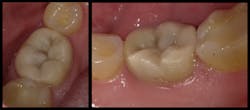

All excess material was removed, and occlusion was checked. The restoration was coated with EQUIA Coat and then light cured. The final result had ideal contours and occlusion (figure 8). At a 23-month recall visit, the tooth was still in occlusion, and minimal wear was noted (figures 9 and 10).

Figure 9: The final restoration at a 23-month recall visit

Figure 10: No. 19, still in occlusion at a 23-month recall visit